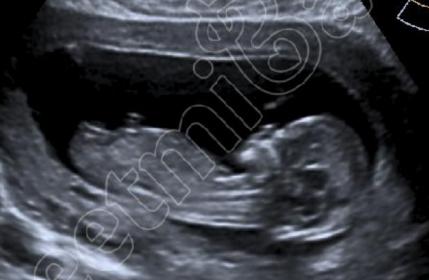

Hi this is my 13week scan. Any guesses of boy or girl? Thank you

I was thinking girl but it would be good to get a better quality photo as this one doesn't zoom well.

These are more I have. Are they any better?

Yeah they are clearer. Still thinking girl :)